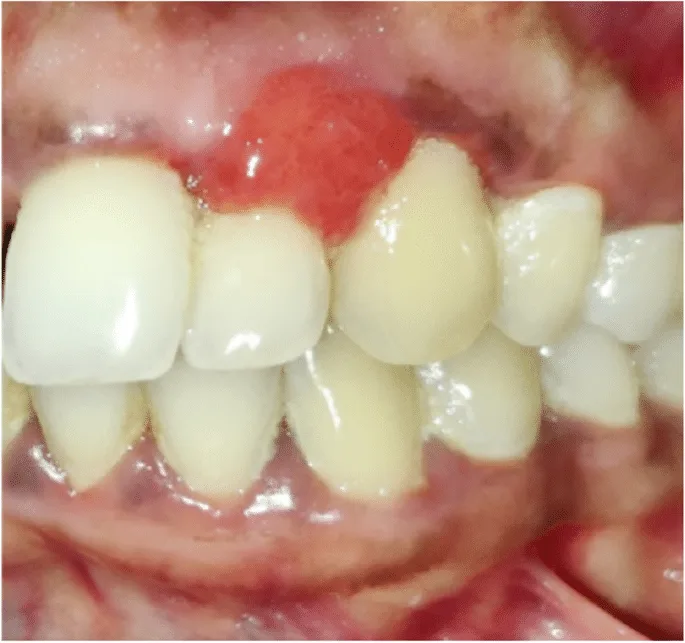

Drug-Induced Acute Gingivitis

Some medications, such as immunosuppressants and oral contraceptives, can cause gingival overgrowth or inflammation. This may lead to enlarged, red gums that bleed easily.